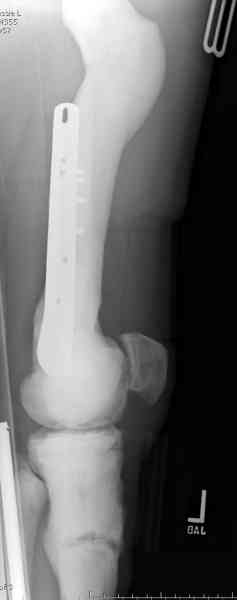

Что-то пациенту как-то не везет по жизни... Тоже самое - интрамедуллярный остеосинтез коротким штифтом для проксимального отдела бедра. Ранняя нагрузка сразу...

Здесь у меня дополнительные снимки с большим разрешением и в разных режимах, а то те дигитал снимки совсем очень блеклые, может, эти изображени изменят выбор тактики

После неудачной попытки скелетного вытяжения в первом мед.учреждении, после осмотра снимков и изучения истории, поставили диагноз “Остеопетроз” или мраморная болезнь, редкая наследственная костная паталогия, где имеется нарушение формации остеокластов.

Конечно, было бы идеальным применение интрамедуллярного остеосинтеза, но учитывая прежний собственный опыт (лечил перелом бедра) и

публикации, предупреждающие о трудностях при обработке кости (иногда из-за неподготовленности инструментария результатом была неадекватная фиксация перелома, или перенос операции из-за фактора усталости оперирующего персонала), решили применить пластину (и в этом же случае был выбран Synthes plate, так что представитель за два дня

зароботал... на десерт тоже).

Заказаны были дополнительные различные дрели, и на следующий день, усиленной бригадой, больного прооперировали, потратив на каждое отверстие около 25-35 минут, хотя сверлили с охлаждением по нарастающей по диаметру сверл и с их заменой каждые 2 мм сверления.

Теперь стоит задача со сращением перелома, из-за отсутствия литературных данных по применению костных стимуляторов при остеопетрозе, и не зная как поведет в этой среде Grafton, все таки надеюсь, что даст толчок к стимуляцию, решил применить пастообразную деминерализованную костную матрицу, расположив спереди между отломками.